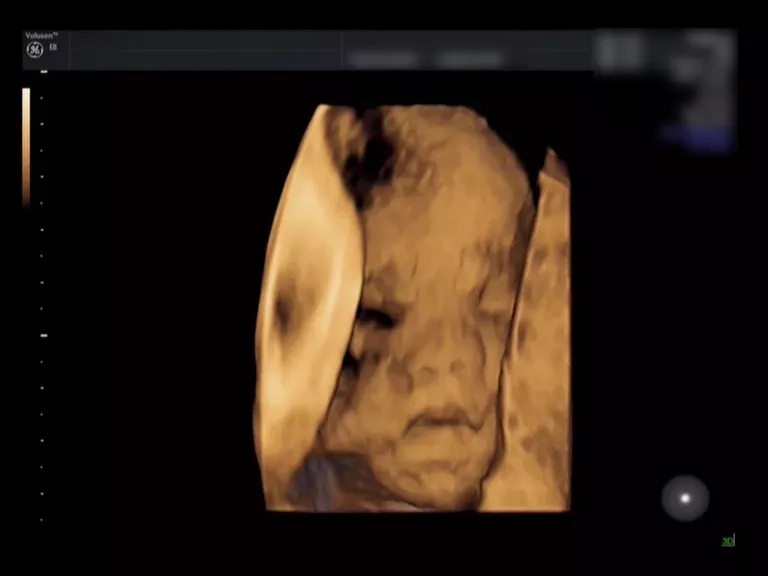

来看这个小baby的彩超对比

就一目了然啦

(三维超声)